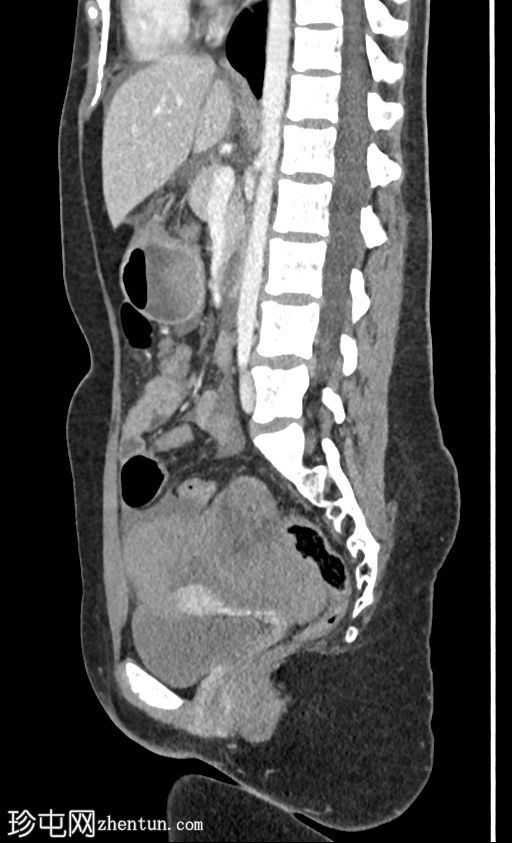

矢状位增强扫描(门静脉期)

2.jpg

右侧附件区可见巨大复杂肿块,伴盆腔血肿及腹水。子宫内可见积液。